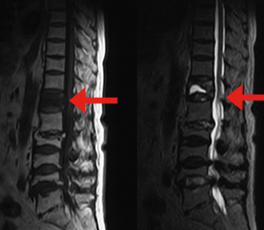

椎体骨折後骨癒合が得られない状態が継続して下肢の脱力が生じています。